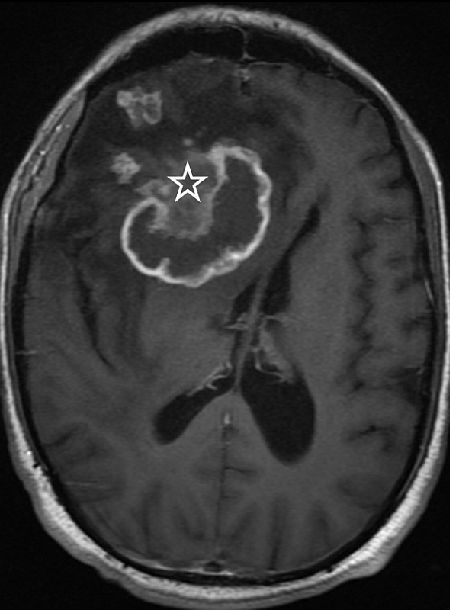

图 B:横断面 MRI T1 像对比增强显示肿块有环状的强化,同时在病变的前部有不均匀强化(图中星号所示),另外还可看到数个散在的点状增强